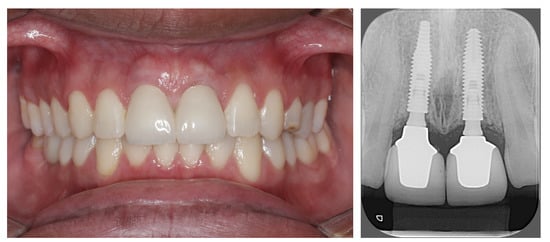

Result and Follow-Up